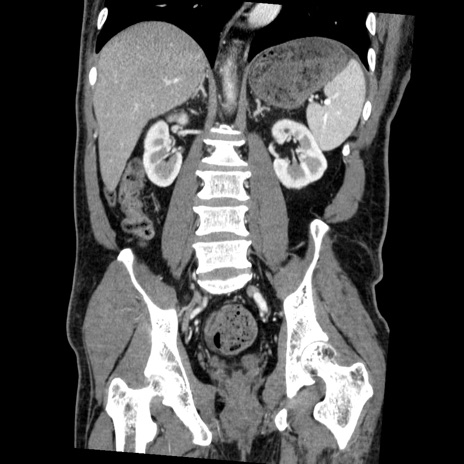

症例22(冠状断像)

【症例】50歳代男性

【主訴】腹痛

【現病歴】AVMからの被殻出血のため回復期リハ病棟入院中。 本日午後3時頃急に下腹部痛が出現した。

【既往歴】AVM、被殻出血、虫垂炎、高血圧

【身体所見】意識晴明、左半身不全麻痺、会話の理解は良好、36.5°C、腹部:膨隆、全体に板状硬、下腹部正中に圧痛点あり、反跳痛-、筋性防御不明、右下腹部にope scar

【データ】WBC 9400、CRP 0.06